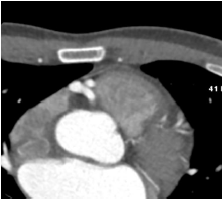

A 40-year-old man presented to the ER with 4 months of progressive dyspnea on exertion and bilateral lower-extremity pitting edema. He had no medical history. EKG-gated computed tomography revealed reduced ejection fraction and a large right coronary artery–to–pulmonary artery fistula. Diuretics improved his symptoms. Examination showed a pansystolic murmur at the left upper sternal border and 1+ pitting edema. He was referred to our hospital for fistula and heart failure management.

Right heart catheterization revealed a pulmonary capillary wedge pressure of 19 mmHg and mean pulmonary artery pressure of 47/27 mmHg. Pulmonary vascular resistance was 3.06 Wood units, with cardiac output of 4.9 L/min and Qp/Qs ratio of 1.24. Coronary angiography showed patent left main, LAD, and circumflex arteries. A small proximal LAD fistula and a large RCA fistula, both draining into the pulmonary artery, were identified.